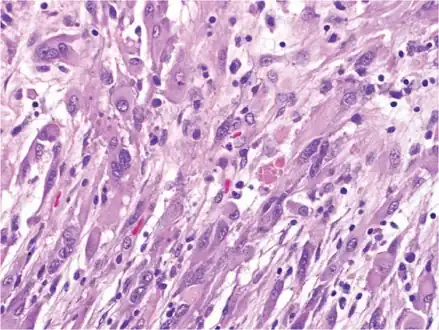

Pleomorphic xanthoastrocytoma (WHO grade II); Pleomorphic xanthoastrocytoma represents a distinctive glioma subtype -

Pleomorphic xanthoastrocytoma, as visualized under a microscope